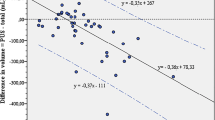

A starting point for the present paper is the linear relationship between bladder volume and the measurement error: SDvolume = a + b × volume. This relationship has been thoroughly documented in three previous studies [2, 3, 4]. When all the cases in these studies are included, the distribution of the SD and residuals supports a linear relationship, which is a prerequisite for using a linear regression function [13] (Figs. 3 and 4).

The SD was calculated when estimating the bladder volume of 120 fetuses. Different methods were used, which gave rise to 222 relationships between SD and bladder volume. The maximum and minimum bladder volumes were 80.5 and 0.1 mL, respectively. The distribution of the SDs supports a linear relationship

The main finding in the present paper is a general formula for calculating the SDHFUPR, which is valid when using 2D ultrasound. As we understand it, this measurement error can only be assessed indirectly by this kind of calculation. The measurement error is made when assessing the volume of the bladder—and only then. When the linear relationship between the bladder volume and measurement error is taken into consideration, there is a specific SDVOLUME related to each estimated volume. The magnitude of the constants a and b depends on the volume assessment method that is used, e.g. 2D ultrasound (ellipsoid and sum-of-cylinders method). The a and b for the ellipsoid method are 0.36516 and 0.09978, whereas they are 0.29911 and 0.02788 for the sum-of-cylinders method. For 3D ultrasound, the relationship between SDVOLUME and the estimated volume is as yet unknown. However, the current paper illustrates the usefulness of this relationship and the implication of using different 2D methods for volume estimation.